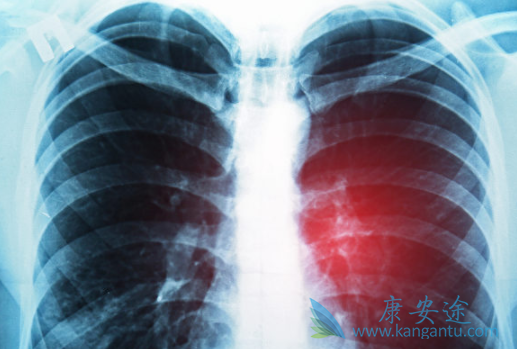

肺癌是全世界发病率和死亡率双高的恶性肿瘤,目前肺腺癌已跃居肺癌首位。恶性胸腔积液是肺腺癌常见的伴随症状,控制胸腔积液能显著提高患者的生存质量。一项研究观察伴有恶性胸腔积液的肺腺癌患者对不同治疗方案的缓解率,结果显示,与单纯化疗相比,恩度联合培美曲塞能显著提高患者的缓解率,对老年患者的生存质量的改善起了重要作用。